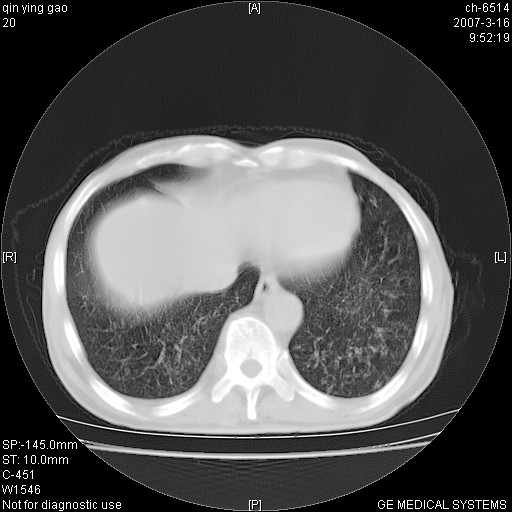

男,64岁.乏力2个月,畏寒、发热1月余。体重下降。血沉加快,白细胞不高。

两肺弥漫分布的斑片状影,部分融合,左肺及纵隔淋巴结见钙化影,考虑1。tb,2。肺泡细胞癌,建议查痰检

两中上肺见有广泛分布大小不一的结节灶及斑片状影,部分融合,双下肺未见异常密度影,纵隔无明显肿大淋巴结,血沉加快,白细胞不高,首先考虑结核。 建议结合ppd检查或痰培养排除其他非特异性炎症。